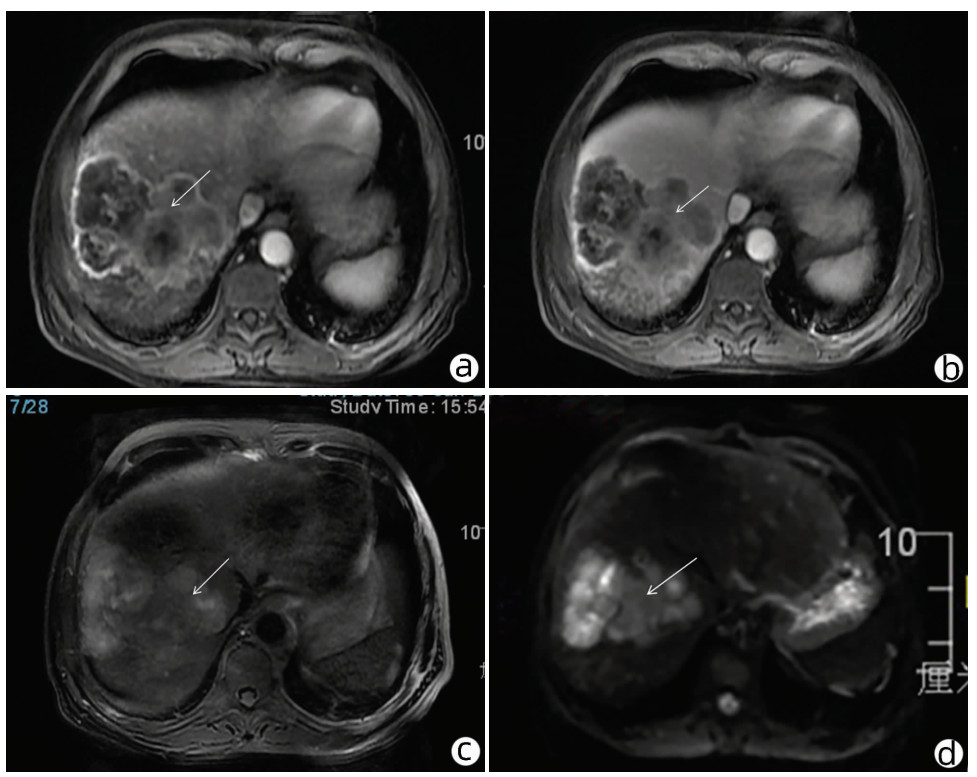

作者贡献声明:雷进负责资料分析,撰写论文;张林枝、陈博文负责提出具体修改意见并进行修改;左石、陆荫英负责拟定撰写思路,指导文章写作并最终定稿。